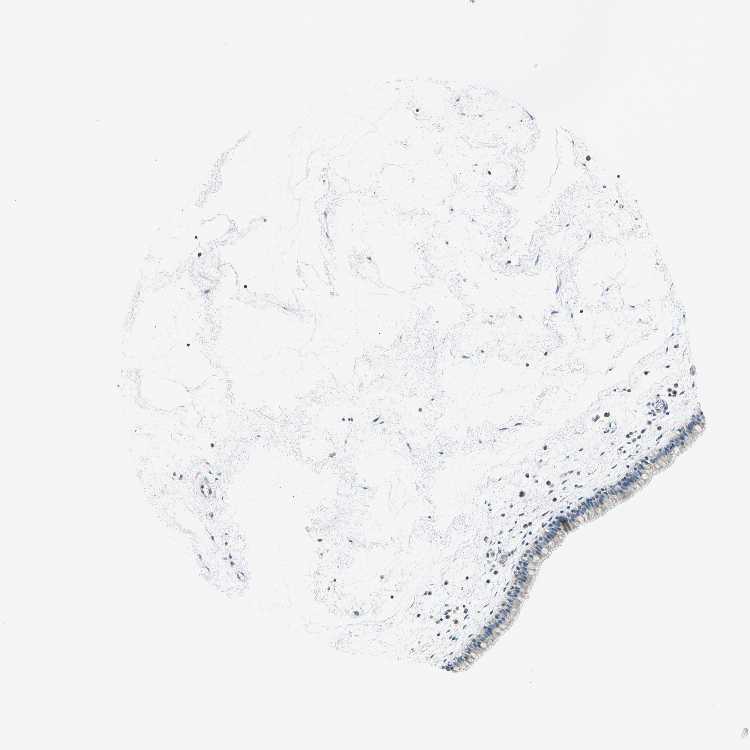

TISSUE PRIMARY DATA NASOPHARYNX Show tissue menu

NASOPHARYNX - Antibody stainingi

Antibody staining in the annotated cell types in the current human tissue is reported as not detected, low, medium, or high, based on conventional immunohistochemistry profiling in selected tissues. This score is based on the combination of the staining intensity and fraction of stained cells.

Each image is clickable and will lead to virtual microscopy that enables deeper exploration of all samples and also displays staining intensity scores, fraction scores and subcellular localization as well as patient and tissue information for each sample.

Antibody HPA004895Antibody CAB013018

Respiratory epithelial cells MediumMedium